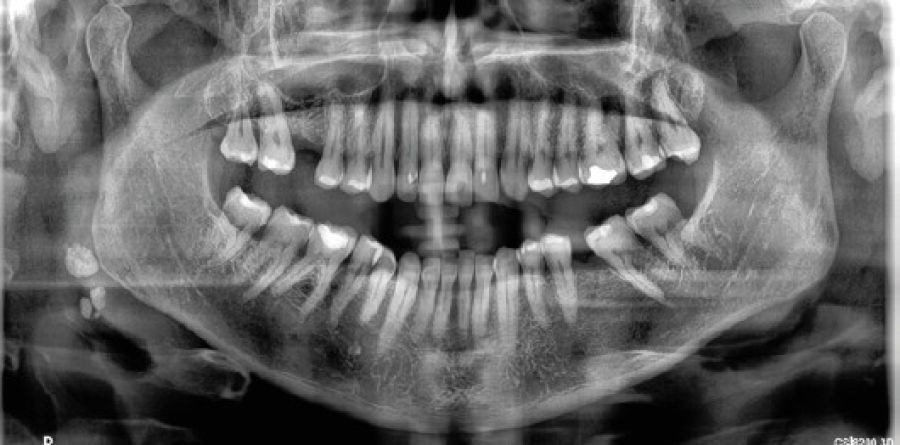

Ante la sospecha de una calcificación al analizar una radiografía panorámica, es crucial realizar un diagnóstico diferencial con otras radio opacidades, ya sean anatómicas o patológicas. En primer lugar, es esencial localizar las estructuras anatómicas normales, como el hueso hioides, la epiglotis, los ligamentos estilomandibulares (Figura 8) o estilohioideos o el cartílago triticeal del tiroides que, a veces, pueden aparecer calcificados. Posteriormente, es necesario diferenciarlas de procesos patológicos, como otro tipo de calcificaciones, que pueden ser provocadas por ateromas en las arterias carótidas o por otros procesos como litiasis de las glándulas salivales (Figura 9), flebolitos, tonsilolitos, o incluso nódulos linfáticos cervicales calcificados16.